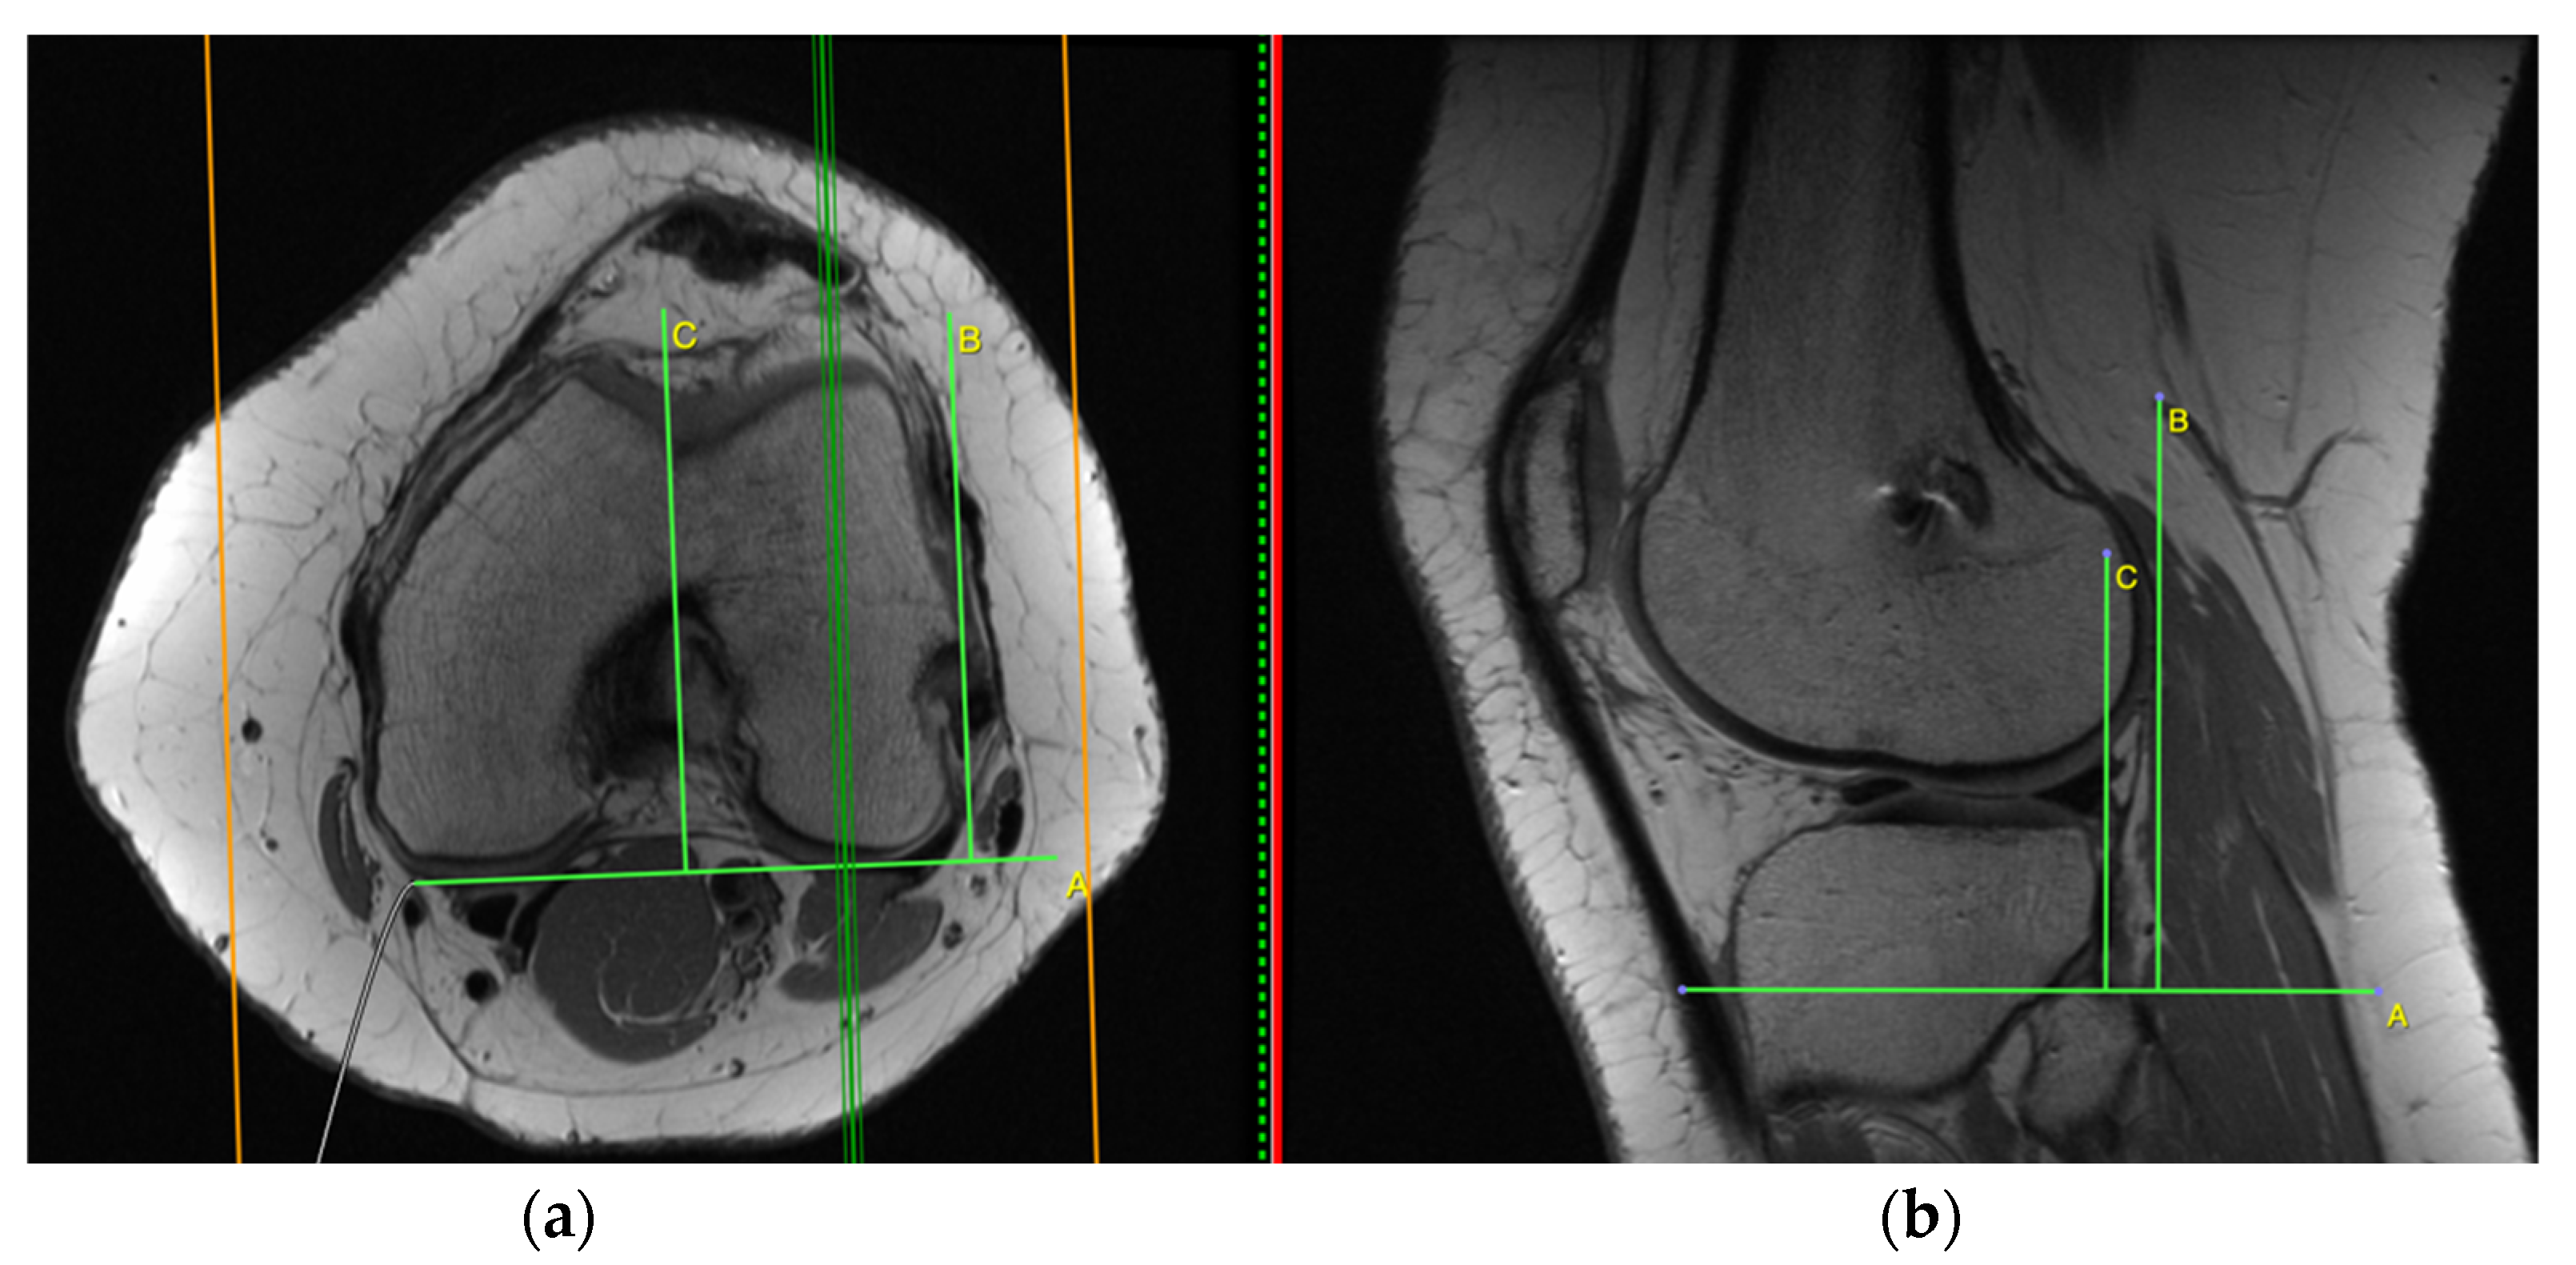

2.2. Measurement on the Axial Plane

3.2.3. Anterior Tibia Subluxation